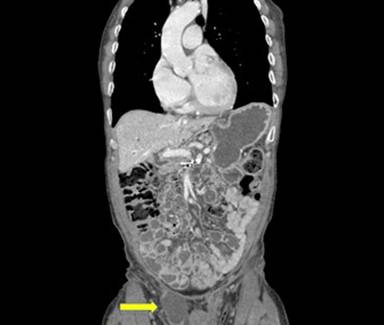

Twenty-one months following pancreaticoduodenectomy, he was evaluated in clinic for a symptomatic right-sided groin mass and a CT scan showed free fluid in the right inguinal canal (Figure 2). He was subsequently taken to the OR and underwent outpatient right-sided hydrocele repair and excision of a non-communicating loculated cyst of the spermatic cord. Postoperatively, he recovered uneventfully. Surprisingly, despite no gross evidence of metastatic disease in the sac, pathology revealed metastatic moderately differentiated adenocarcinoma consistent with a pancreaticobiliary primary (Figure 3, 4, 5).

Figure 2. CT-scan of the abdomen and pelvis showing right-sided inguinal fluid collection. |